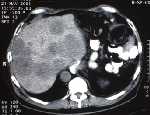

Abb. 2: Fallbeispiel zur Anwendung von Imatinib bei einem gastrointestinalen Stromatumor (GIST): 63-jähriger Patient mit GIST des Magens; Erstdiagnose 11/96. Initial Gastrektomie und Splenektomie. Zustand nach Metastasenentfernung in der Leber 9/99. Systemische und intrahepatische Chemotherapie intermittierend von 12/99 bis 03/01; darunter kontinuierliche Tumorprogression. Therapiestart mit Imatinib ab Ende Mai 2001. Die computertomographischen (CT) Aufnahmen (oben) zeigen eine Größenabnahme der Lebermetastasen sowie bereits zu diesem angegebenen Zeitpunkt nach vier Wochen eine Dichteabnahme der Lebermetastasen, die im weiteren, nicht dargestellten Verlauf noch zystischer imponieren. Zeitlich korrespondierend mit den oben dargestellten CT Aufnahmen zeigt sich in der 18FDGpositronen- emissions-tomographischen (PET-) Untersuchung (unten) ein weitgehender Rückgang der FDG-Aufnahme im Bereich der Lebermetastasen als Ausdruck einer Inaktivierung des Stoffwechsels der Tumorzellen unter der Therapie mit Imatinib. (oberer Pfeil: Leberregion; unterer Pfeil: Harnblase mit normaler FDG-Darstellung)

Die CT-/PET-Aufnahmen wurden freundlicherweise zur Verfügung gestellt von Dr. P. Gocke (Zentralinstitut für Röntgendiagnostik) / Dr. S. P. Müller und Dr. J. Kanja (Klinik für Nuklearmedizin), beide Universitätsklinikum Essen